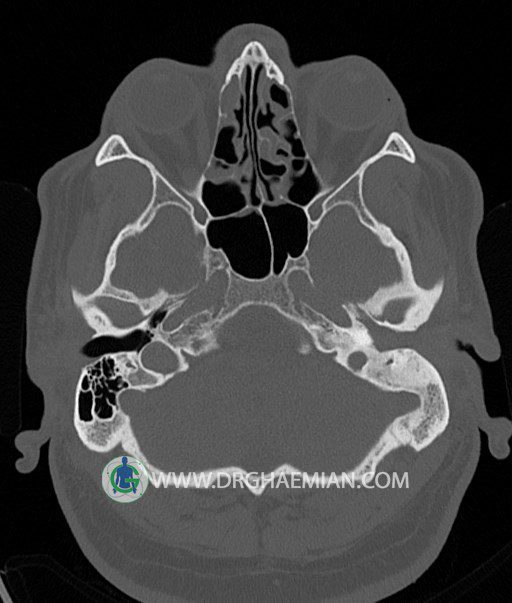

سی تی اسکن گوش داخلی به رادیولوژیست اجازه می دهد تا سطوح مختلف، یا اسلایس هایی از استخوان های که از جمجه به گوش می روند را از طریق امواج ایکس چرخشی مشاهده کند. در این کیس اودیت مدیا، ماستوئیدیت مزمن، اوتیت خارجی، انحراف سپتوم بینی، کونکا بولوزا و افزایش ضخامت سینوس ها مشاهده می شود.

در HRCT از استخوان تمپورال با مقاطع آگزيال ، ساژيتال و کرونال ظريف ( 0.6 mm ) :

– نماي کوکلهآي دو طرف با 2.5 دور گردش مجرا

– نماي cochlear aqueduct

– نماي semicircular canal خلفي ، لترال ، فوقاني و وستيبول

– استخوانچه هاي گوش داخلي شامل malleus ، incus و stapes (دنسيتي و رديف استخوانچه ها )

– نماي oval window و round window ، tympanic cavity ، attic و کانال گوش داخلي

– کانال عصب فاشيال و مسير ان از ناحيه کانال گوش داخلي ، geniculate ganglion تا محل خروج ان از stylomastoid foramen

– نماي tympanic membrane ، کانال ICA ، بولب جوگولار دو طرف

در حد طبيعي است .

– اپاسيتي گوش مياني چپ ناشي از وجود دانسيته نسج نرمي دراطراف استخوانچه ها همراه با اروژن اسکوتوم و

استخوانچه ها بدون جابجايي در رديف استخوانچه ها مشهود است که مطرح کننده اوتيت مديا همراه با نشانه

هاي مشکوک به کولستئاتوم مي باشد .

– اپاسيتي و اسکلروزيس ماستوئيد چپ نشانه ماستوئيديت مزمن

– اپاسيتي کانال گوش خارجي ناشي از دانسيتي نسج نرمي مطرح کننده external otitis

– انحراف سپتوم مياني بيني به راست

– کونکا بولوزا در کونکاي مياني چپ و

– افزايش ضخامت مخاطي در سينوس هاي اتموئيد و ماگزيلاري

اپاسيته